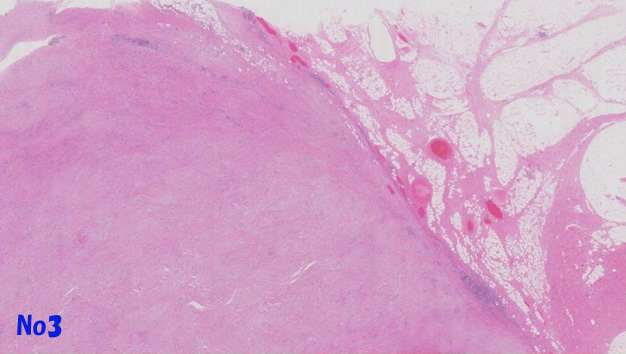

他の部分では異型細胞は, リンパ濾胞がよく発達した豊かな膠原線維性またはfibromyxoidな間質を伴って増殖しておりsclerosing and/or inflammaory variants of well differentiated liposarcomaの所見を呈する(Virtual Slide-No.3 and No.4) 。metaplastic ossificationが一部に認められた(Virtual Slide-No.5) 。

no3a.jpg